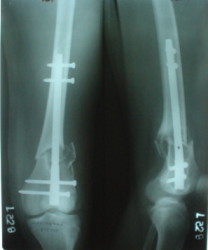

I attached an example of C2 fracture with result of the same technique in 5 months.

This is great. I would never have thought of doing antegrade nailng for such a #. I would also have never dreamt of such range of flexion.

The mobilisation of knee is started immediately from the second day. Weight bearing is permitted as in any other interlocked nailing. That is, Toe touch to start with and within four days, partial to in another two weeks, full weight bearing. Of course that is assuming that the correct size nail has been used. Up to 70 kg body weight, 11no will be good enough and 12mm if more.Usually at the 1st followup, at 6 weeks time, they have full flexion..I